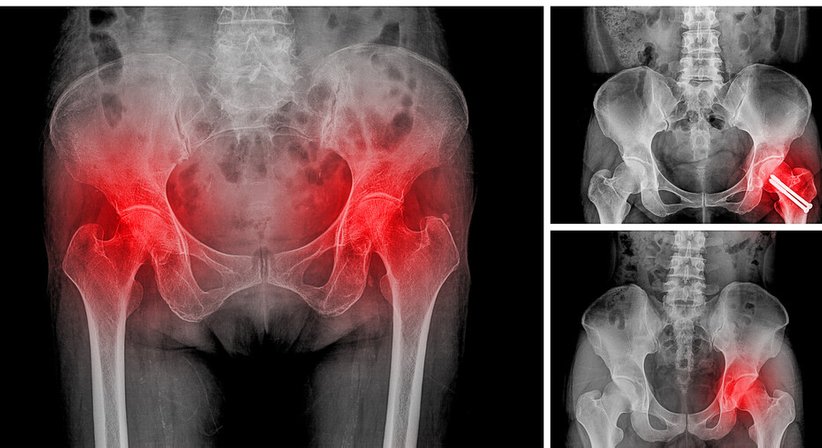

Als Ursache für Hüft- und Leistenschmerzen kommen neben einem geschädigten Hüftgelenk oder Hüftinstabilitäten auch chronische Muskelverspannungen, Bindegewebsverklebungen oder beispielweise auch Schleimbeutelentzündungen in Frage. Akut auftretende Hüftschmerzen sollten in jedem Fall ärztlich abgeklärt werden. Auch bei hartnäckigen chronischen Schmerzen sollten Sie sich an einen Orthopäden wenden.

Im Zentrum der Abklärung akuter und chronischer Hüft(gelenks)schmerzen steht eine entsprechende Funktionsprüfung und eine sorgfältig durchgeführte Anamnese. Durch den Einsatz von hochauflösenden bildgebenden Verfahren kann die Ursache oft schon durch eine umfassende Untersuchung in der Praxis ermittelt werden.